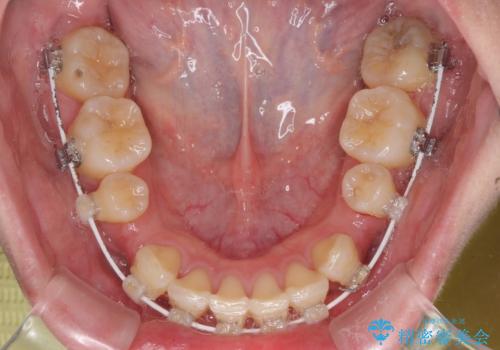

- 矯正装置

- 審美装置

左右ともに下顎に対して上顎歯列が前方位にある上顎前突であったので、上顎歯列全体を後方に移動させることで上下咬み合わせを改善し、その上で抜歯矯正により口元の突出感を改善させていきました。